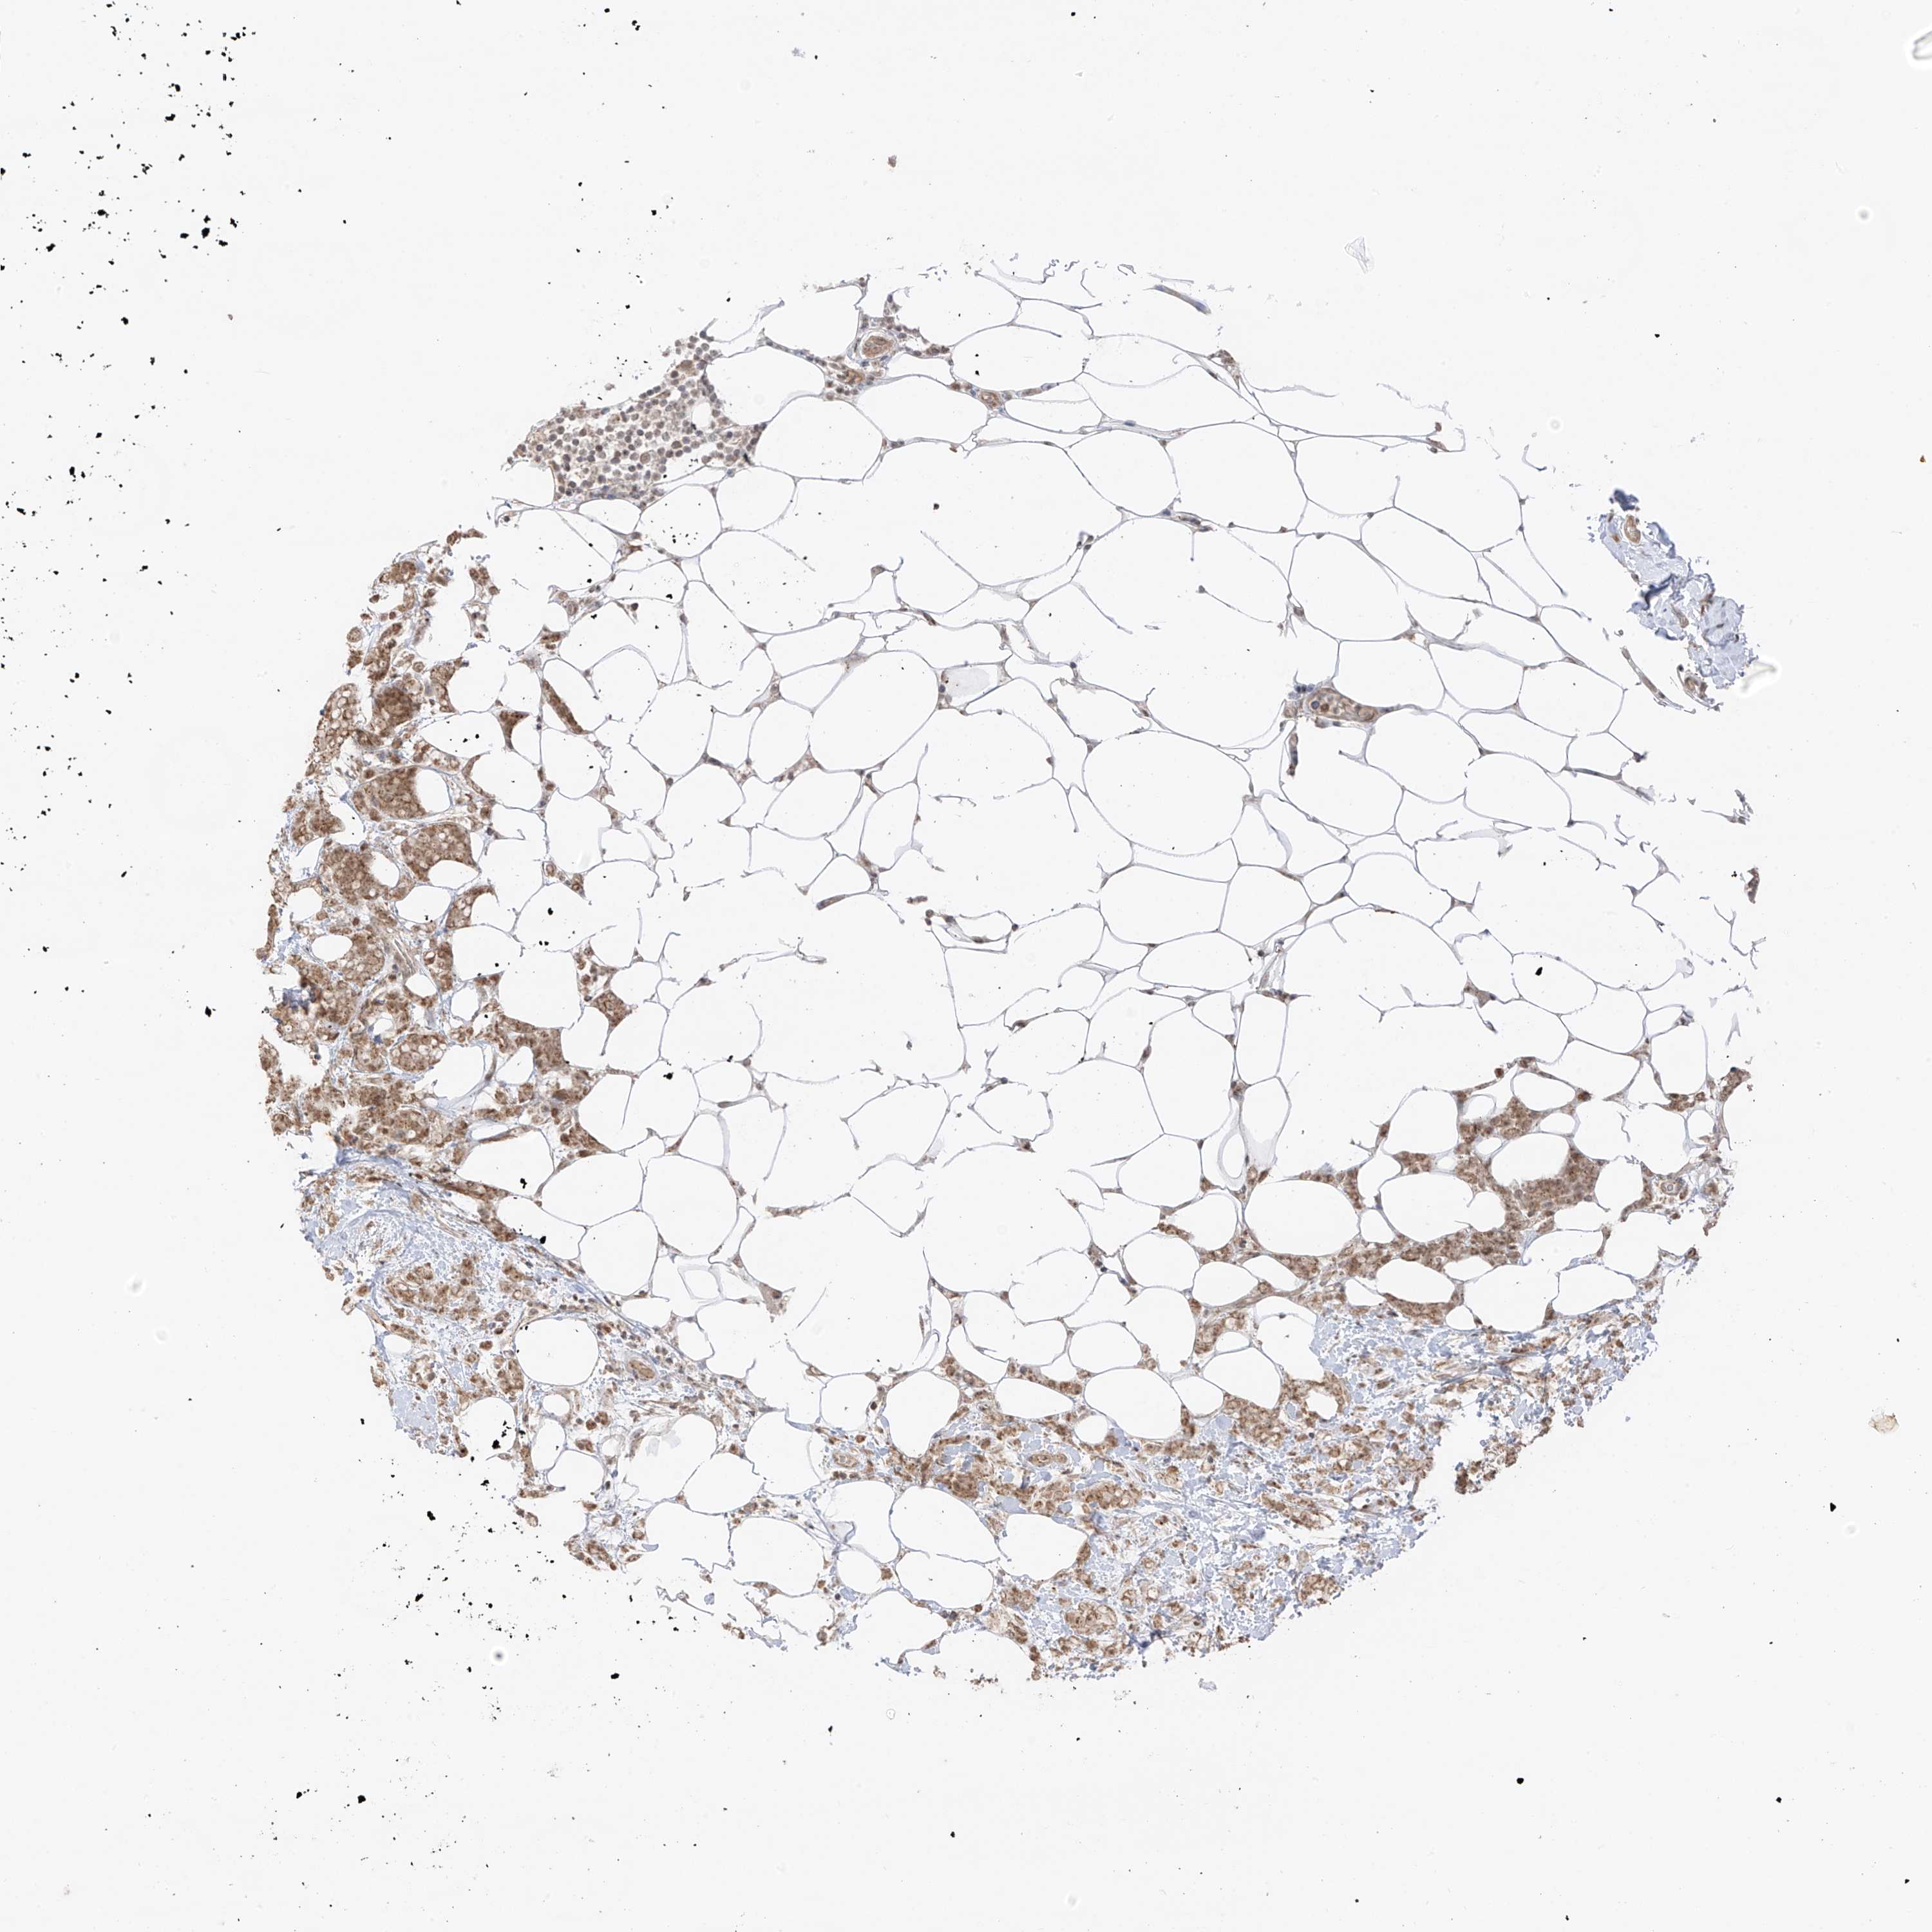

CANCER BREAST CANCER Show tissue menu

BRCA TCGA BRCA VALIDATION PROTEIN EXPRESSION